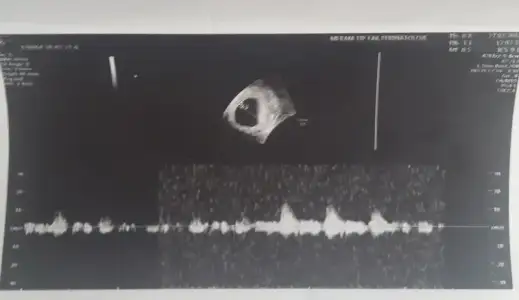

Evet doktorun dediği gibi aslında..bu sefer Allah korusun Bebeğini canım dua edelimtest yaptı progestan seviyesi normal çıktı . erken gebelik olduğu için düşecek ise her şekilde düşecek dedi. sadece içerde kalmasını uzatacaz dedi geçen seferde öyle olmuştu ilaç kullandığım halde düşmüştü.şimdi bekliyorum dua edip yapcak başka bişi yok